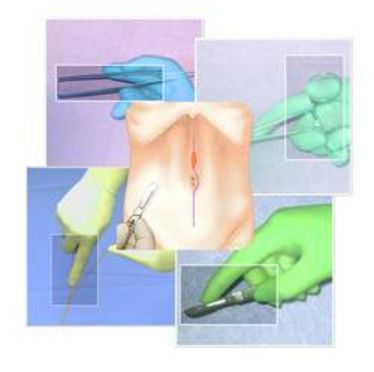

24.10.2013

BASIC SURGICAL SKILLS

BASIC SURGICAL SKILLS

BASIC SURGICAL SKILLS

BASIC SURGICAL SKILLS

BASIC SURGICAL SKILLS

BASIC SURGICAL SKILLS